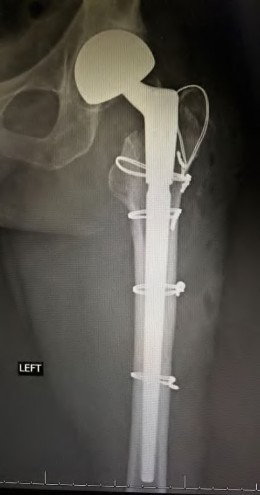

A 72-year-old female presents with progressive left thigh and knee pain for the last year. 5 years ago she sustained a femoral neck fracture treated with the implant seen in Figures A-C (current radiographs). The thigh pain is worse with weight-bearing. C-reactive

protein and erythrocyte sedimentation levels are within defined limits. Which of the following is the most likely cause of her pain?